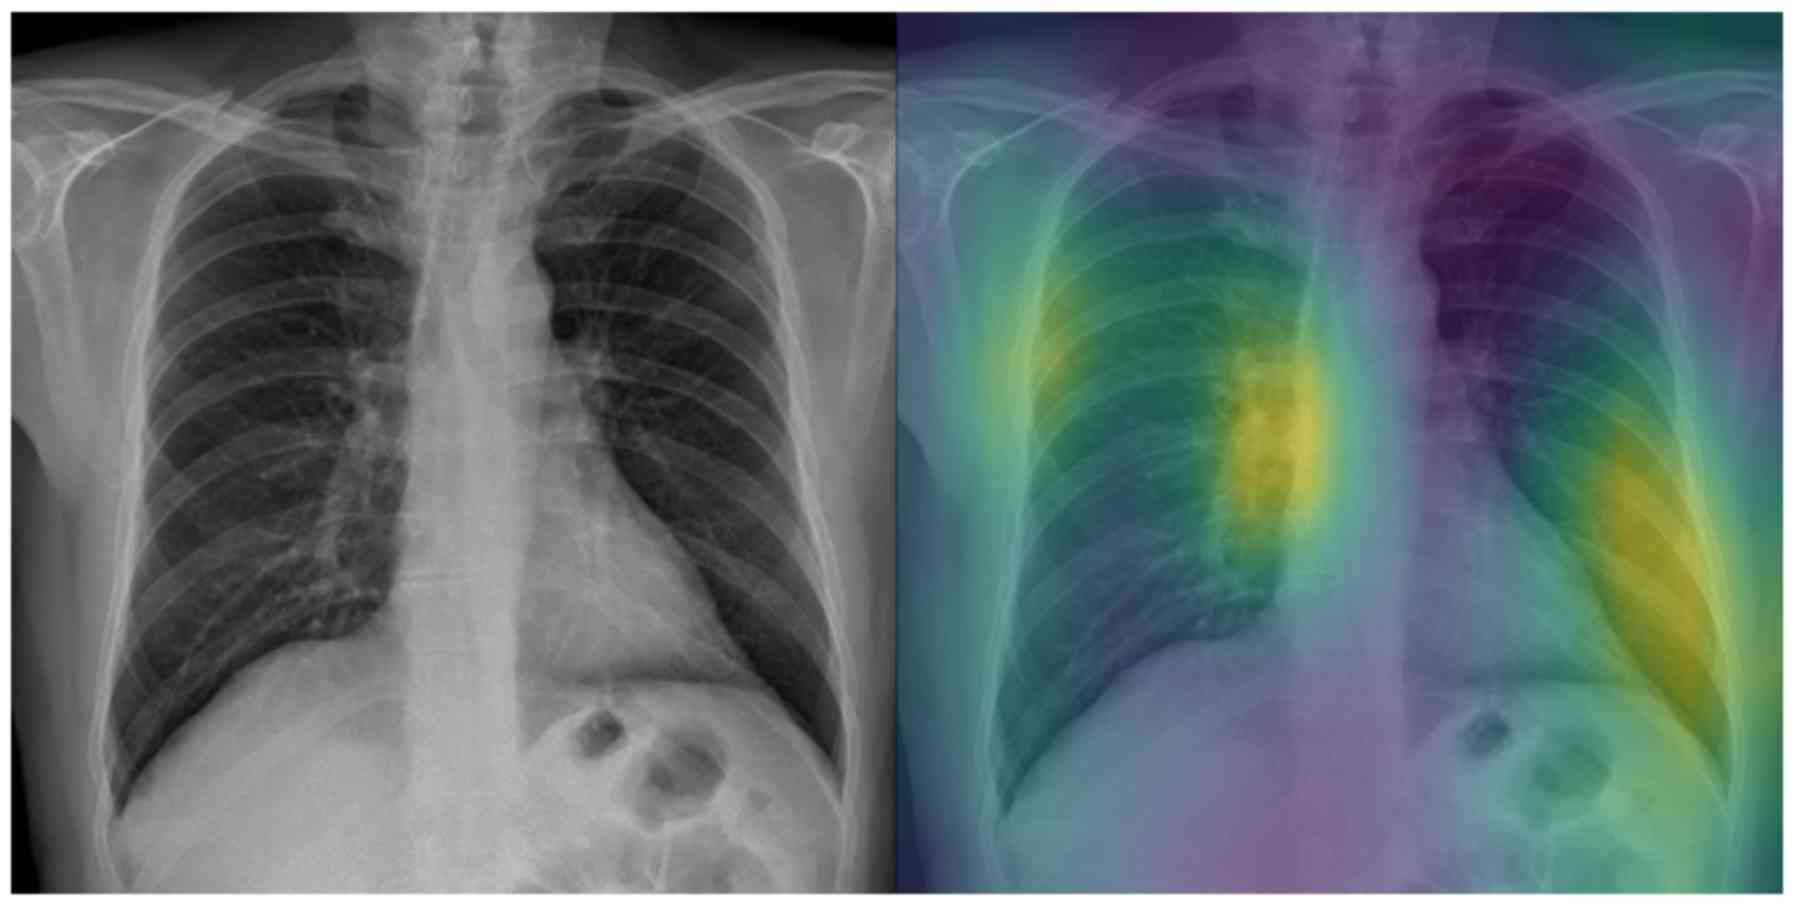

Interpretable artificial intelligence framework for COVID‑19 screening on chest X‑rays

COVID-19 has led to an unprecedented healthcare crisis with millions of infected people across the globe often pushing infrastructures, healthcare workers and entire economies beyond their limits. The scarcity of testing kits, even in developed countries, has led to extensive research efforts towards alternative solutions with high sensitivity. Chest radiological imaging paired with artificial intelligence (AI) can offer significant advantages in diagnosis of novel coronavirus infected patients. To this end, transfer learning techniques are used for overcoming the limitations emanating from the lack of relevant big datasets, enabling specialized models to converge on limited data, as in the case of X‑rays of COVID‑19 patients. In this study, we present an interpretable AI framework assessed by expert radiologists on the basis on how well the attention maps focus on the diagnostically‑relevant image regions. The proposed transfer learning methodology achieves an overall area under the curve of 1 for a binary classification problem across a 5‑fold training/testing dataset.